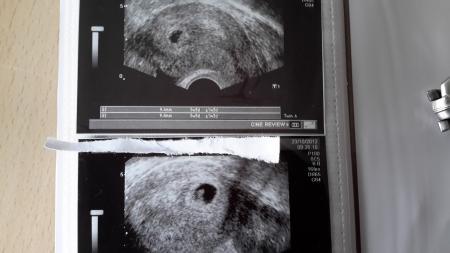

Hallo, komme aus dem KH..konnte es nicht aushalten....es war eine Fruchthülle zu sehen und Dottersack.....gut dachte ich...5+4 ........dann sagte die Ärztin..ja, ich muss es ja sagen....das ist jetzt nicht eine normale runde Form der Fruchthülle wie wir sie kennen...sie benannte meine als Eierform ( kann ich so gar nicht erkennen....dachte die sieht doch gut aus...eher etwas oval woobei die Enden jeweils nicht abgerundet sind sondern gerade runter gehen....mit etwas Fantasie könnte man sie evtl. auch als kleines Auto sehen........ach ich weiss nicht wie ich es beschreiben soll....hatte das jemand von euch und ist es doch wieder ein Indiz dass es wieder keine intakte ss ist?? Danke

Weisst, im Krankenhaus hätten die solche Aussagen nicht sagen müssen. Wozu? Meine Mamimsagte immer, alles was sicht nicht weiter entwickelt wäre natürliche Auslese des Körpers... und sie hat sechs Kinder, drei Abgänge! Nun den, hab jetzt mal mein erstes Bild zur Hand genommen. Bei 5+ aus der Kiwu klinik nach IVF. Und rund ist meine Fruchthöhle auch nicht gewesen Erst eine woche später, mit wachsen des Embryo ich bin sicher, das nächste mal wird es auch bei dir anders aussehen Wird schon. LG

Bild zu